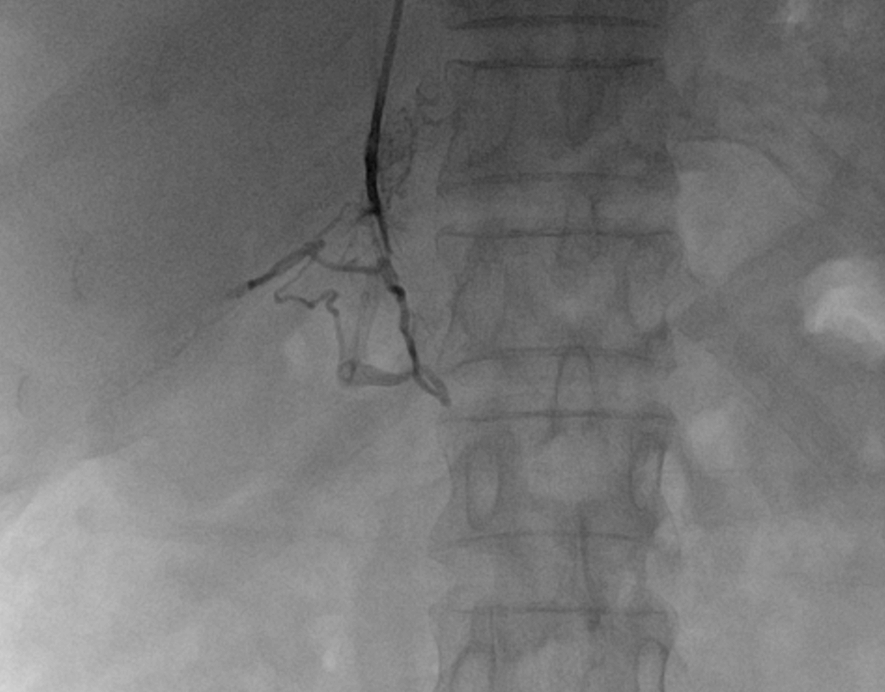

双侧肾上腺静脉取血提示右侧肾上腺为优势分泌侧。经与泌尿外科充分术前讨论,鉴于其右侧腺瘤体积较小,且合并左侧增生,外科手术切除腺瘤较困难,且患者拒绝外科手术治疗,故予右侧肾上腺动脉栓塞治疗。

(历时30分钟成功施行经皮选择性肾上腺动脉栓塞术)